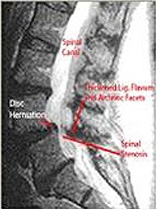

동시에 척추관을 구성하는 후관절돌기, 추궁, 황색인대 등에서도 변성이 오면서 두꺼워져서 척추관 전후, 좌우 사방이 좁아지며 여기에 척추가 전방 또는 후방으로 휘어 척수와 신경근을 직접 누르고 혈류 장애를 일으켜 증상이 나타나게 됩니다.

이와 같은 퇴행성 척추관 협착증은 운동량이 많은 요추와 경추에서 잘 발생되고, 흉추에서는 드뭅니다.